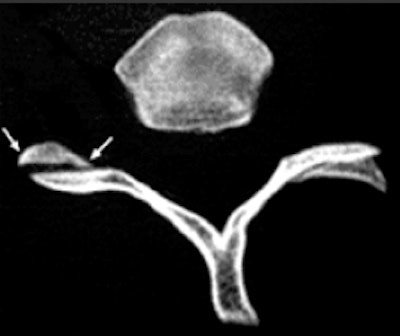

On CT, the vertebral facet joint space can look like a hamburger. All images courtesy of Fathima Hasan Mohamed.

Hamburger: "My own personal favorite," Mohamed commented. On axial CT, the vertebral facet (apophyseal) joint space can look like a hamburger. When the facet joint is dislocated, the articular facets become uncovered, or naked, and this is also called naked facet sign. This CT sign is characteristic of a flexion-distraction injury and indicates severe ligamentous disruption and spinal instability. It may be unilateral or bilateral, depending on the facet dislocation.